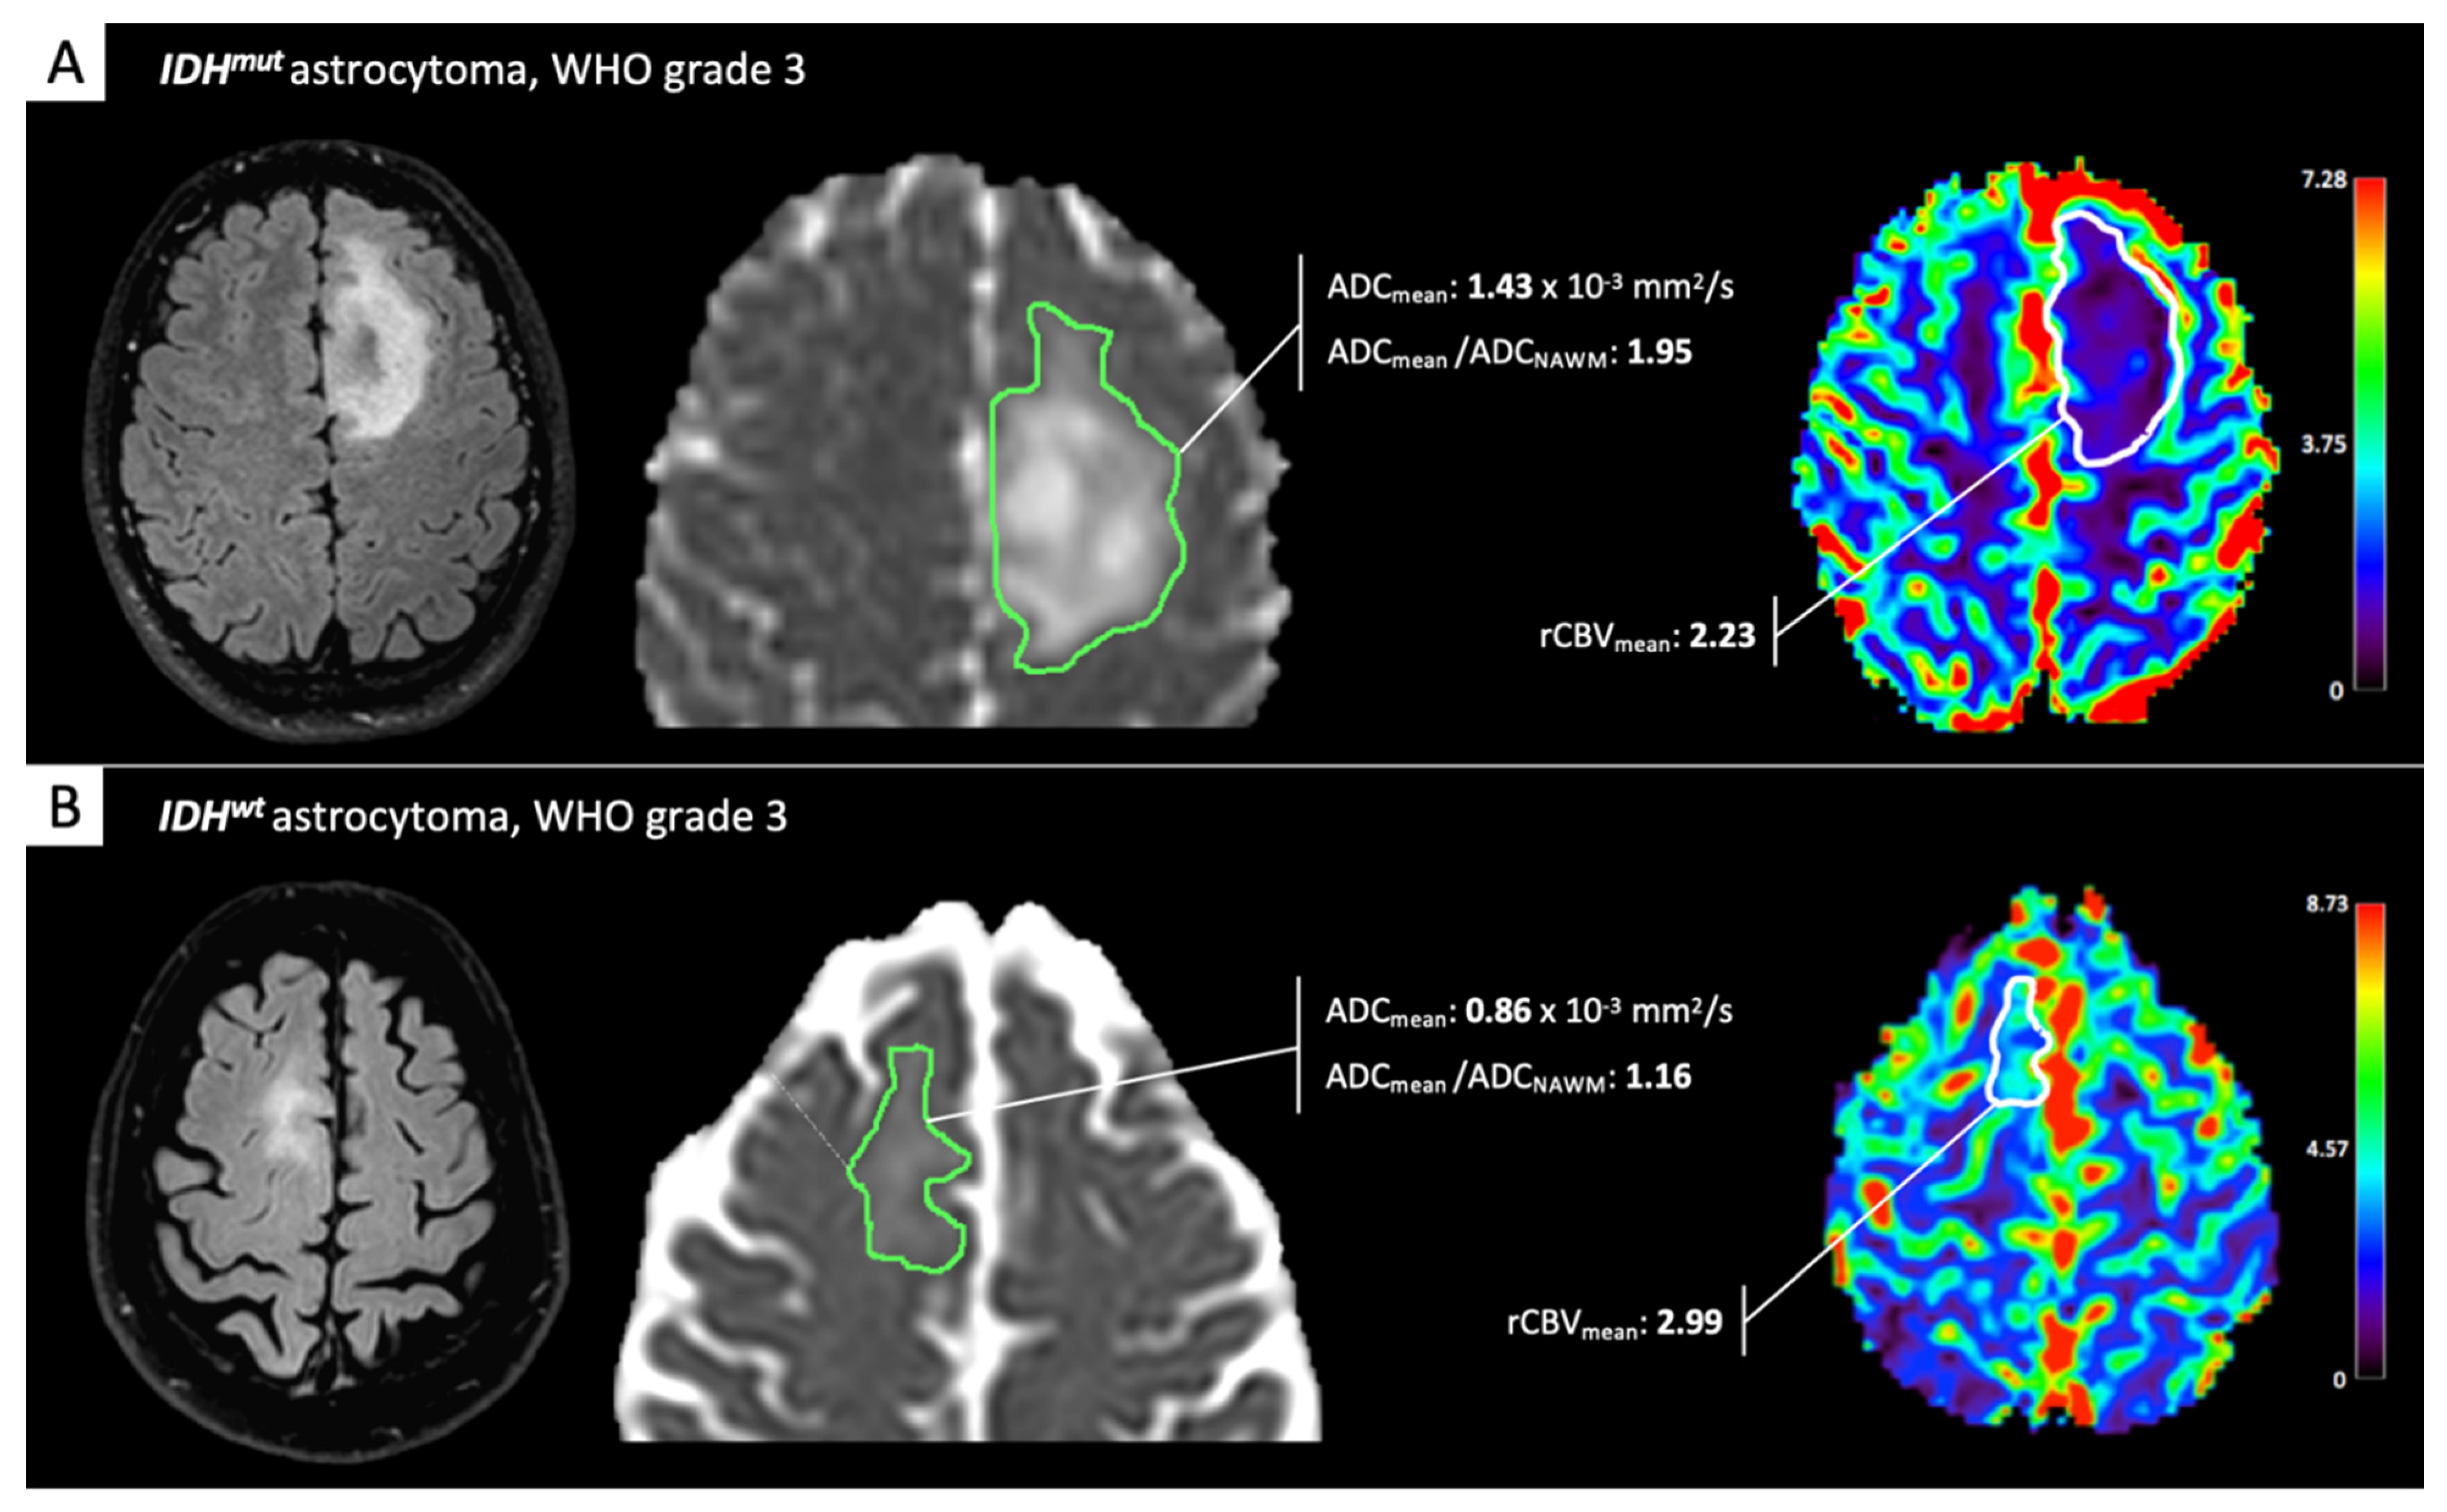

The aforementioned studies, taken together, seem to advocate for a rather high reliability of ADC and PWI for IDH-status prediction in LGG. However, many authors [11,25,26,27] demonstrated that the diagnostic performance of aMRI for IDH-status in LGG significantly increases when combined in multimodality analyses and/or with cMRI features. ADC- and/or rCBV-measures have been variously combined with cMRI features—such as tumor volume, enhancement, and location, and presence of calcifications, cysts, or T2FM—with very good to excellent diagnostic performance for IDH-determination (AUC ranging 0.84–0.96 across studies). Maynard and colleagues [27], for instance, obtained strong results on a large LGG cohort (study/test sample: 290/49 patients), by developing two models based on ROI-derived ADCmean/ADCNAWM combined with the patient’s age, tumor location and enhancement pattern, and presence of calcifications (model-A, AUC 0.96) or cysts (model-B, AUC 0.94). Figure 1 shows two representative cases (one IDHmut- and one IDHwt-LGG, respectively) for which diffusion and perfusion features were evaluated through a clinically feasible single-slice ROI approach.

Figure 1.

Perfusion and diffusion assessment of lower-grade glioma (LGG). MRI datasets were retrieved from the archive of our Institution. Diffusion MRI (dMRI) and perfusion-weighted imaging (PWI) features from one isocitrate dehydrogenase mutant (IDHmut)-LGG (A) and one IDH wild type (IDHwt)-LGG (B) were evaluated through a clinically feasible single-slice region of interest (ROI) approach. IDHwt-LGG exhibits more “aggressive” aMRI features, in particular a mean apparent diffusion coefficient (ADCmean)/normal-appearing white matter (ADCNAWM) ratio lower than 1.8, the proposed cutoff for IDHwt status prediction by Maynard et al. [27] and Thust et al. [28].